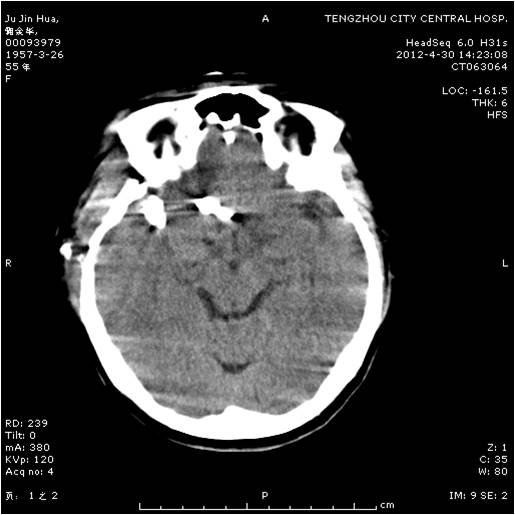

動(dòng)脈瘤夾閉術(shù)前 動(dòng)脈瘤夾閉術(shù)后